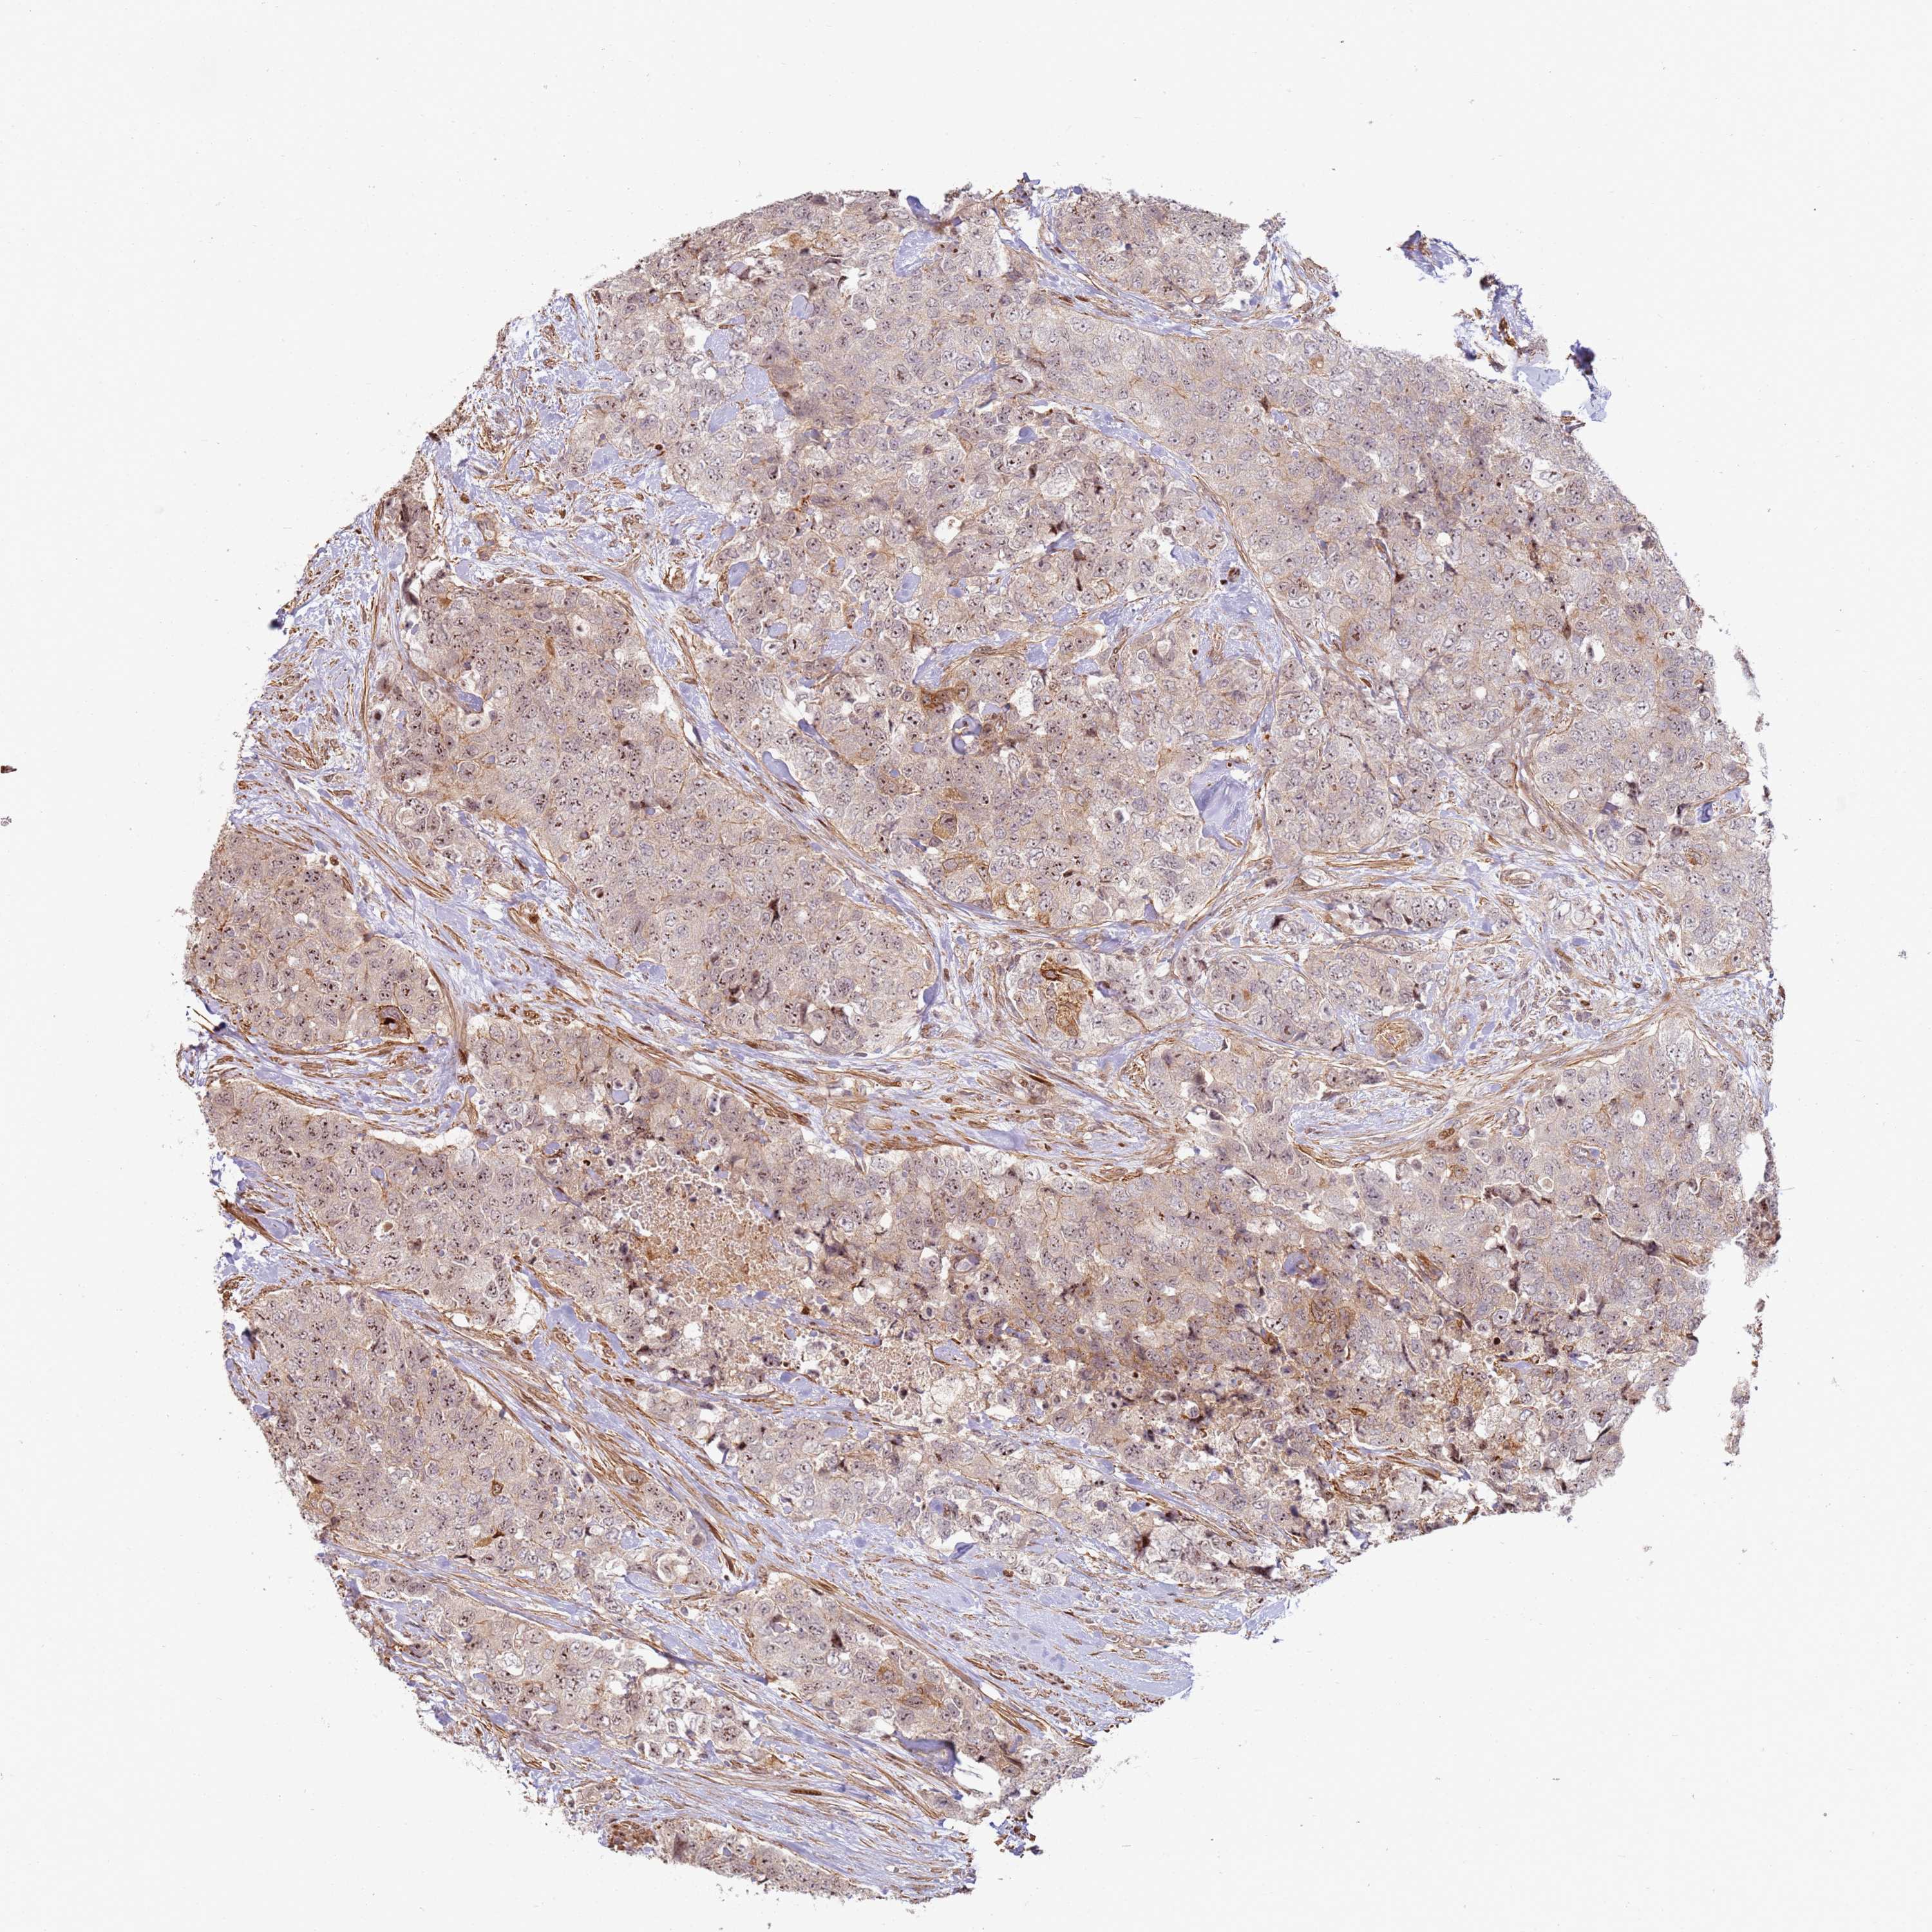

UROTHELIAL CANCER - Protein expressioni

A mouse-over function shows sample information and annotation data. Click on an image to view it in a full screen mode. Samples can be filtered based on level of antibody staining by selecting one or several of the following categories: high, medium, low and not detected. The assay and annotation is described here.

Note that samples used for immunohistochemistry by the Human Protein Atlas do not correspond to samples in the TCGA dataset.

Antibody stainingi

Antibody staining in the annotated cell types in the current human tissue is reported as not detected, low, medium, or high, based on conventional immunohistochemistry profiling in selected tissues. This score is based on the combination of the staining intensity and fraction of stained cells.

Each image is clickable and will lead to virtual microscopy that enables deeper exploration of all samples and also displays staining intensity scores, fraction scores and subcellular localization as well as patient and tissue information for each sample.

Antibody HPA047506

Staining

High

Medium

Low

Not detected

Intensity

Strong

Moderate

Weak

Negative

Quantity

>75%

75%-25%

<25%

None

Location

Nuclear

Cytoplasmic/membranous

Cytoplasmic/membranous,nuclear

Urothelial carcinoma, High grade

Urothelial carcinoma, Low grade